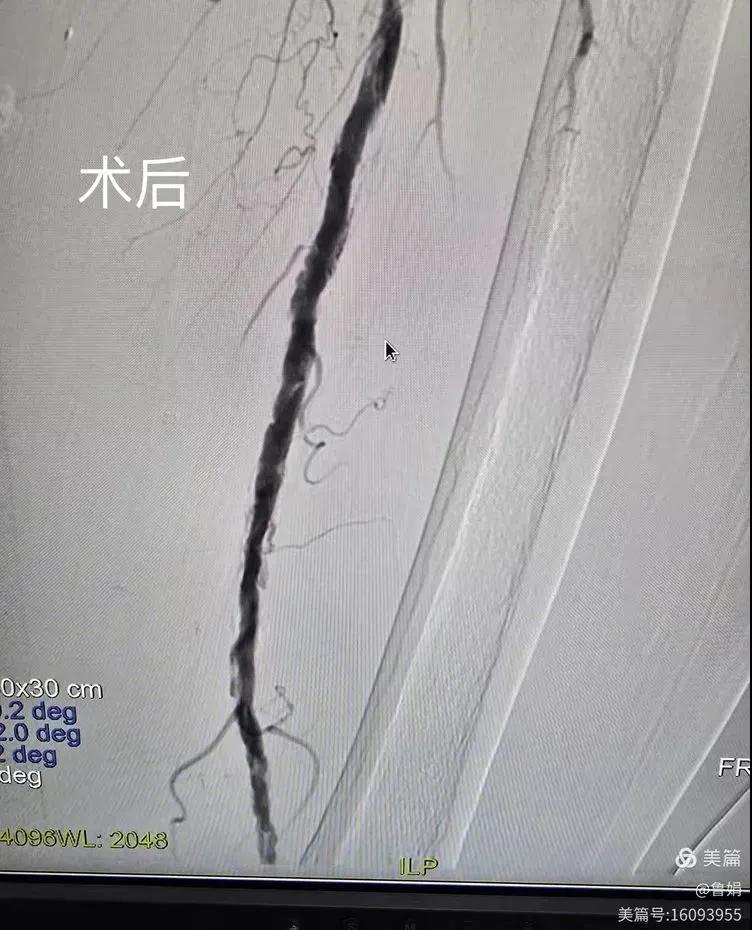

據悉,該患者,女,73歲,下肢動脈硬化閉塞癥,“以靜息痛,間歇性跛行”入院,CTA評估:股淺動脈,腘動脈間斷性多段重度狹窄,外二科血管外科團隊根據患者病情,結合檢查結果,經過科室會診后,決定對該病人行介入治療。手術由周創業副主任與北大一院血管外科專家郭宏杰教授聯合開展,對股淺動脈,腘動脈重度閉塞段行血管開通+藥涂球囊擴張成形,術后狹窄明顯緩解,血流恢復!